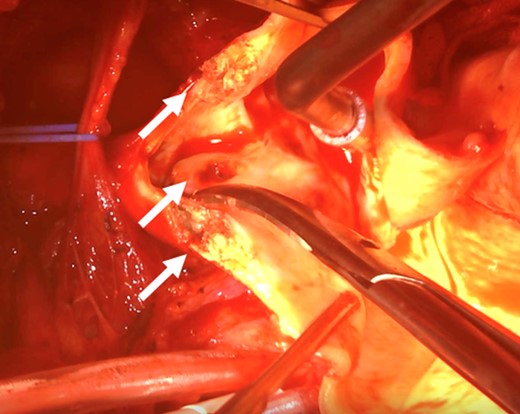

After admission, carotid ultrasonography revealed a large, soft plaque with ulceration in the IA and a very mobile soft plaque in the LSA (Fig. 3). EVT was thus considered too dangerous, and TAR using a four-branched prosthesis was planned. Intraoperatively, bilateral axillary arteries were initially exposed, and an 8-mm vessel prosthesis was anastomosed. Median sternotomy was then performed. Cardiopulmonary bypass was established with arterial perfusion via bilateral axillary arteries and bicaval venous drainage. TAR was performed under hypothermic circulatory arrest with antegrade selective cerebral perfusion, then the brachiocephalic artery and LSA were clamped and the left common carotid artery (LCA) was intubated. To avoid hoarseness due to injury of the left recurrent laryngeal nerve, a hybrid prosthesis (FROZENIX, Japan Lifeline, Tokyo, Japan) was used and a distal anastomosis was created between the LCA and LSA. The LCA was ligated and the prosthesis, which was anastomosed to the left axillary artery, was brought into the mediastinum and anastomosed with a branch of the four-branched prosthesis (Fig. 4). The postoperative course was uneventful and the patient was discharged on postoperative day 16 (Fig. 5).

A soft plaque with ulceration in the IA (A, B) and a very mobile soft plaque in the LSA (C, D).